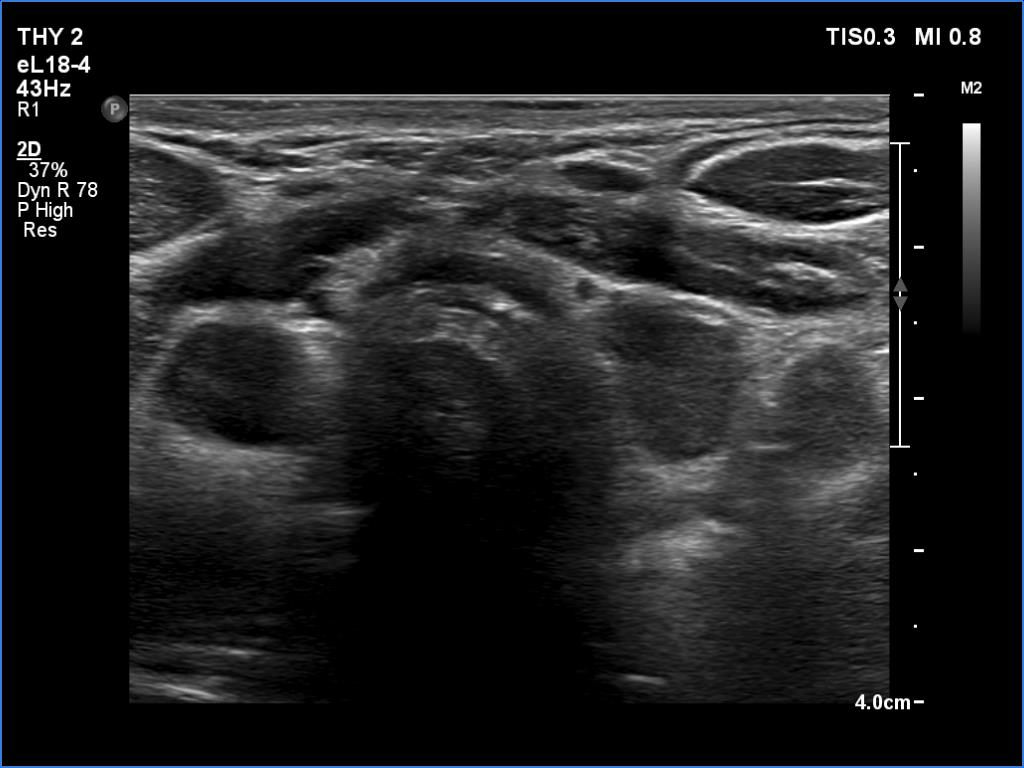

Follow-up examination 8 years later (4th and 5th rows of images):

Clinical data: The patient was referred for evaluation of a continuously increasing thyroglobulin level which resulted in 2.86 ng/mL, 5.74 ng/mL and 20.1 ng/mL, at the 2-yr, 5-yr and 7-yr follow up. Cytology of enlarged lymph nodes, multiple CT-scans and PET-CTs failed to reveal recurrence.

Palpation: There were two palpable, firm but freely moveable masses in the right and left submandibular area.

Ultrasonography revealed hypoechoic discrete lesions in both thyroid lobes. The lesions presented microcalcifications. Corresponding to the palpable mass in the right submandibular region, a reactive-type regular lymph node was found. There was an enlarged lymph node in the left submandibular region. The node had a regular hilum but displayed a heterogeneous pattern.

Comment. Until the final histological examination is completed, I would like to draw attention to two things. One is the heterogeneity of the left lymph node and the other is the size and structure of the lesions in the thyroid beds - these features are suspicious of thyroid cancer.